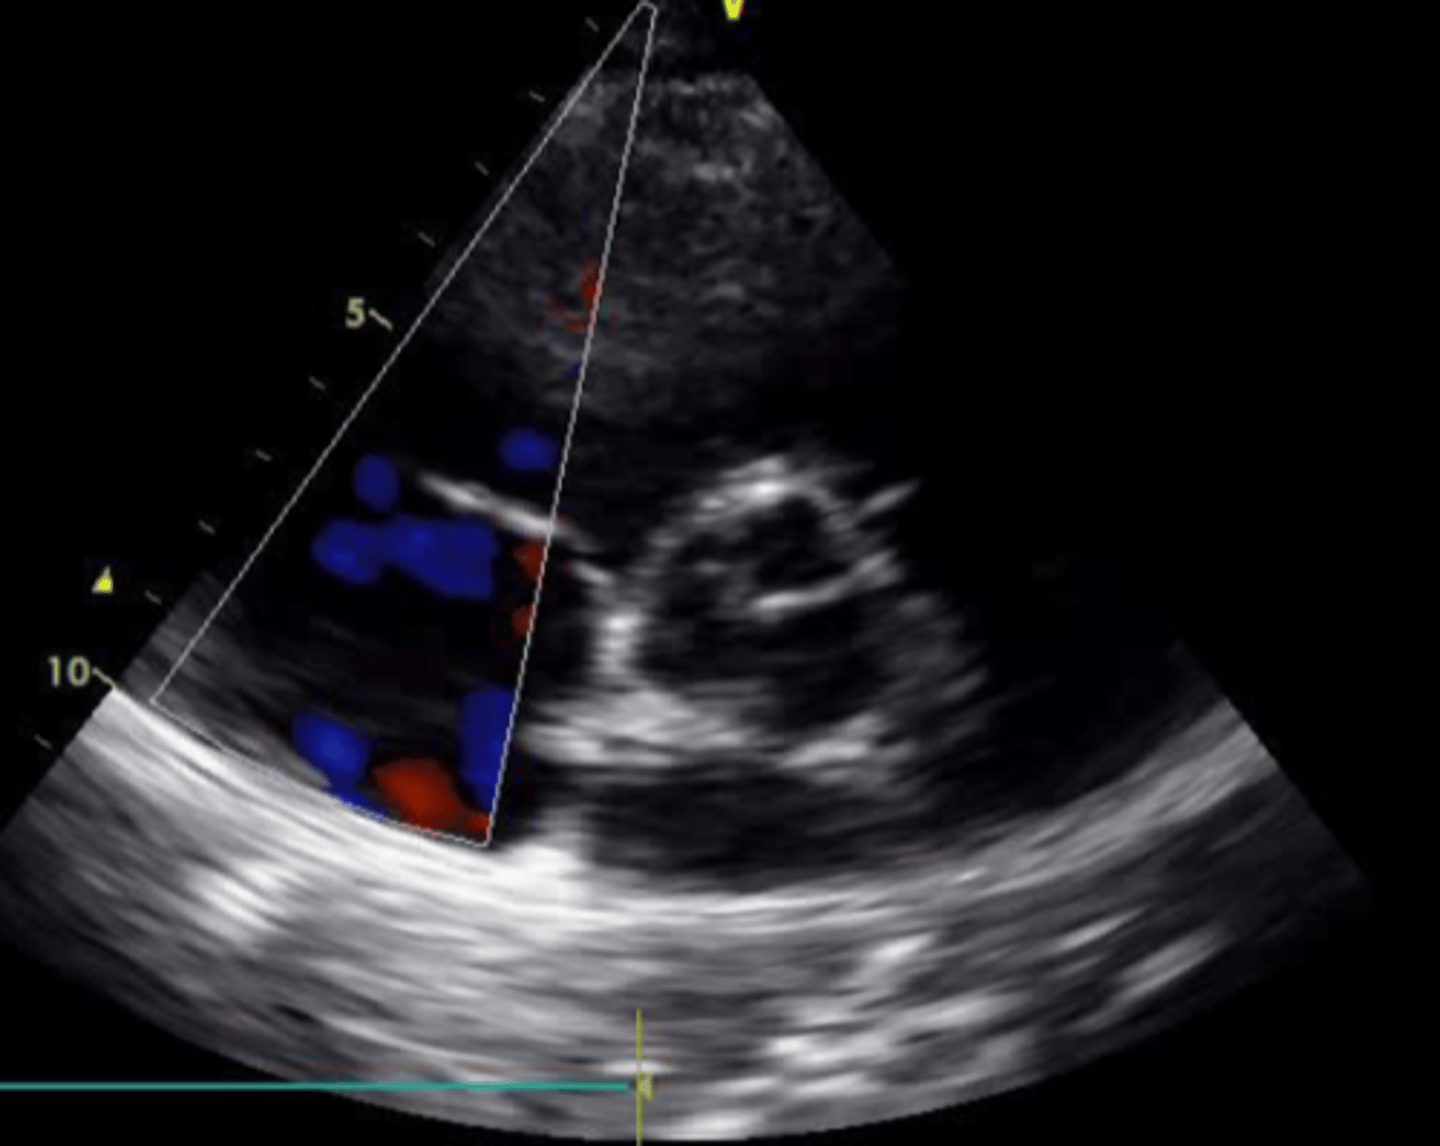

posterior mitral valve leaflet

left leaflet

anterior mitral valve leaflet

right leaflet